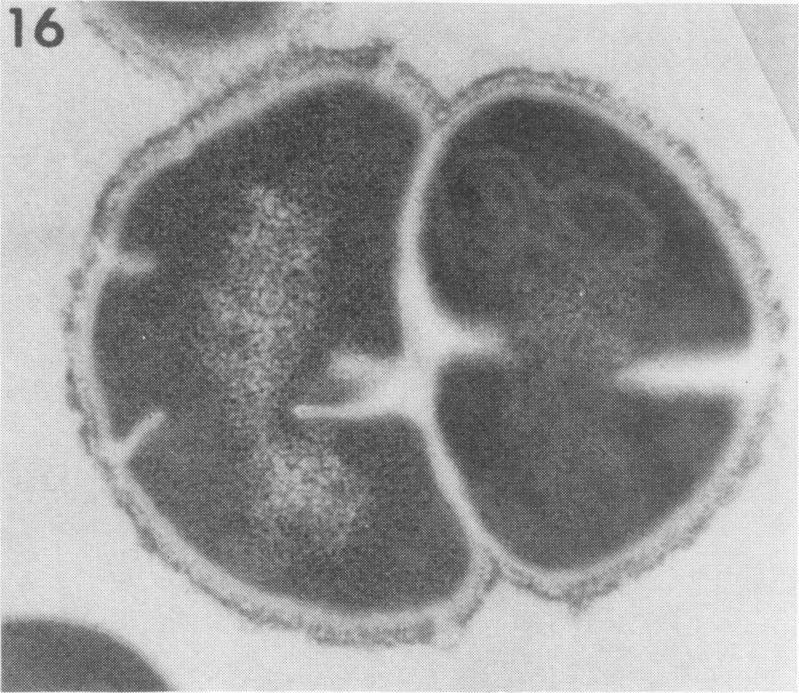

Ultrastructural alterations brought about by treatment of a beta-hemolytic streptococcus with a bactericidal substance from Staphylococcus aureus are described and illustrated. The substance causes an early condensation of nucleoid deoxyribonucleic acid (DNA) and a partial loss of ribosomes. These changes are followed by a dissolution of the cell contents resulting in bacterial "ghosts" composed of empty cell wall and capsule. These morphological findings correlate with known biochemical effects of the bactericidal substance on ribonucleic acid degradation and cessation of DNA and protein synthesis.

本文描述并图示了用金黄色葡萄球菌的杀菌物质处理β-溶血性链球菌引起的超微结构改变。该物质导致核体脱氧核糖核酸(DNA)早期凝聚和核糖体部分丢失。这些变化之后,细胞内容物溶解,导致由空细胞壁和荚膜组成的细菌“幽灵”。这些形态学发现与杀菌物质对核糖核酸降解以及 DNA 和蛋白质合成停止的已知生化效应相吻合。